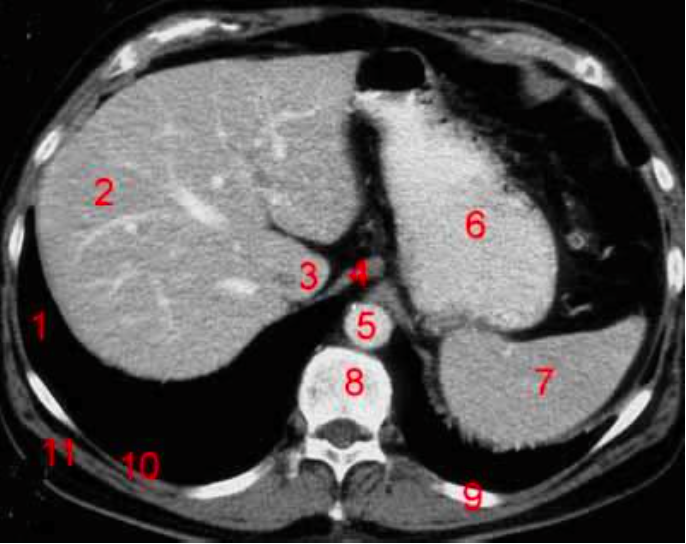

2

Number 1?

R Kidney

3

4

Perfectly

Q

Number 2?

A

IVC

How well did you know this?

1

Not at all

5